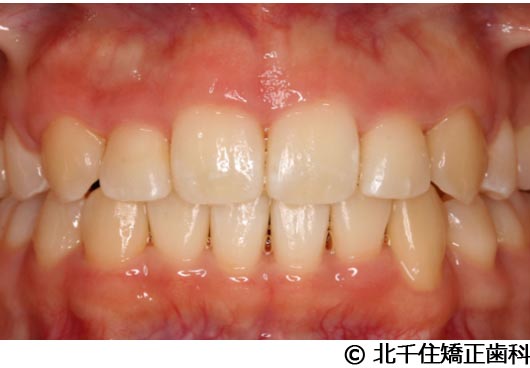

【症例2】上顎前突症

- 治療前

- 治療中

- 治療後

- 治療名

- 上顎前突症

- 費用

- 1,399,000円(税込)

- 期間

- 3年6ヵ月

- 治療回数

- 42回

- 通院頻度

- 1ヵ月ごと

- 年齢・性別

- 19歳10ヵ月・男性(初診時)

治療内容

-

患者様の症状

主訴:出っ歯、口元の突出、横顔をきれいにしたい

治療方法

骨格性の上顎前突、上下顎第一小臼歯4本及び上顎第二大臼歯を抜歯して矯正用アンカースクリューを併用してワイヤー矯正治療(セラミックブラケット)。

治療結果

骨格性上顎前突に対し、抜歯および矯正用アンカースクリューを併用した矯正治療により歯列および咬合関係の調整を行った症例である。治療後は保定装置を使用し、歯列および咬合の安定維持を目的として定期的な経過観察を行っている。

※治療結果は個人差があります。

治療を行う上での注意点(リスク・副作用)

歯磨き不良に伴うカリエスや歯周病、顎関節症、歯根吸収など。